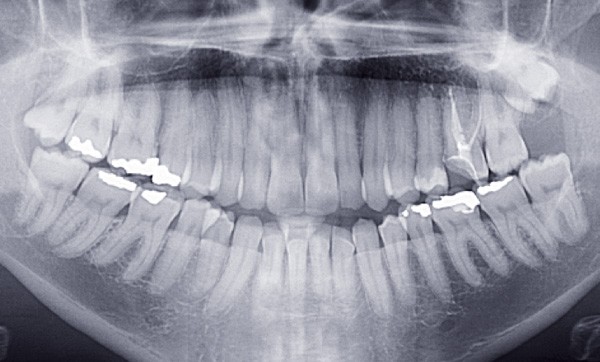

L’orthodontiste confronté au traitement d’une béance dentaire antérieure se retrouve souvent face à un défi. Ces traitements comptent parmi les plus difficiles en orthodontie. Le cas est-il chirurgical ? Peut-on le traiter directement avec de l’orthodontie ? Faut-il extraire ? Si l’analyse des éléments diagnostiques va orienter nos choix, le contexte fonctionnel, souvent marqué, compliquera les choses, et mettra peut-être en péril la stabilité des résultats.

Le choix d’extraire ne doit absolument pas être systématisé [5]. Il n’existe pas de « candidat idéal » ! Les béances sont souvent associées à un excès vertical de la partie inférieure de la face. Ce contexte ne permet pas, alors, au patient de fermer ses lèvres naturellement en position de repos, ce qui favorise une respiration buccale avec une position basse et antérieure de la langue. Ce dysfonctionnement va entretenir la béance. La prise en charge du patient avec une rééducation de la musculature oro-faciale est une condition essentielle à la stabilité du traitement à venir.

Les extractions dentaires seront privilégiées, comme l’ont décrit Sarver et Weissman, dans les cas d’hyperdivergence modérée, sans sourire gingival marqué, et de biproalvéolie associée à une biprochéilie [10]. La fermeture de la béance dentaire sera alors facilitée par la réduction de la biproalvéolie. Et la compétence labiale sera favorisée par la réduction de la biprochéilie. Le Graal sera l’obtention de la fermeture du compas mandibulaire par notre mécanique orthodontique. Dans ce but, les extractions de molaires ou de deuxièmes prémolaires seront privilégiées [1]. La mésialisation des dents postérieures sera recherchée afin de diminuer…